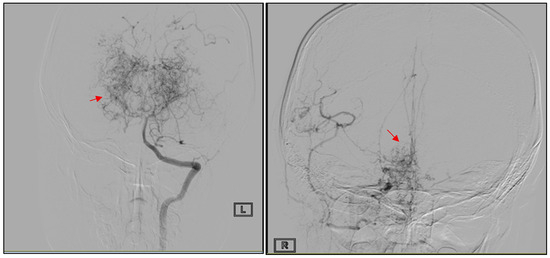

Figure 1

Background: Moyamoya disease (MMD) is a rare, progressive cerebrovascular arteriopathy characterized by stenosis and occlusion of the distal internal carotid arteries with the development of compensatory collateral networks. In children, MMD is a major cause of ischemic stroke; however, neurological morbidity frequently extends beyond cerebrovascular events to include epilepsy, headache, cognitive impairment, and psychiatric manifestations. Data regarding the long-term evolution of these complications in Caucasian pediatric patients remains limited. Case Report: We present the longitudinal case of a Caucasian female diagnosed with advanced MMD after an ischemic stroke at the age of 7 years, followed by indirect surgical revascularization (encephalo-duro-arterio-synangiosis) and chronic antiplatelet therapy. Four years later, she developed recurrent focal aware sensory–motor seizures associated with chronic post-ischemic cortical injury. Despite stable vascular imaging and absence of recurrent infarction, the patient experienced persistent neurological sequelae, including residual spastic hemiparesis, episodic tension-type headaches, and evolving neuropsychological complications. Cognitive assessment initially suggested mild neurocognitive impairment, with subsequent improvement during adolescence. In late follow-up, prominent anxiety symptoms emerged, and psychiatric evaluation confirmed panic disorder requiring psychological and pharmacological support. The patient remained neurologically stable into adulthood under continued multidisciplinary care. This case illustrates the broad spectrum of neurological and psychiatric complications that may accompany pediatric MMD, even in the absence of new ischemic events. The accompanying literature review emphasizes that epilepsy, headache, cognitive dysfunction, and psychiatric disorders represent clinically significant components of the long-term disease burden in children with MMD. Conclusions: Pediatric moyamoya disease should be regarded not only as a cause of childhood stroke, but also as a chronic condition with long-term epileptic, cognitive, and psychiatric sequelae that may evolve independently of recurrent ischemic injury. By providing longitudinal follow-up from childhood into adulthood in a Caucasian patient, this report underscores the importance of integrating neuropsychological and psychiatric surveillance into standard care pathways, alongside vascular and surgical management, to better address the full spectrum of morbidity and improve quality of life. Full article